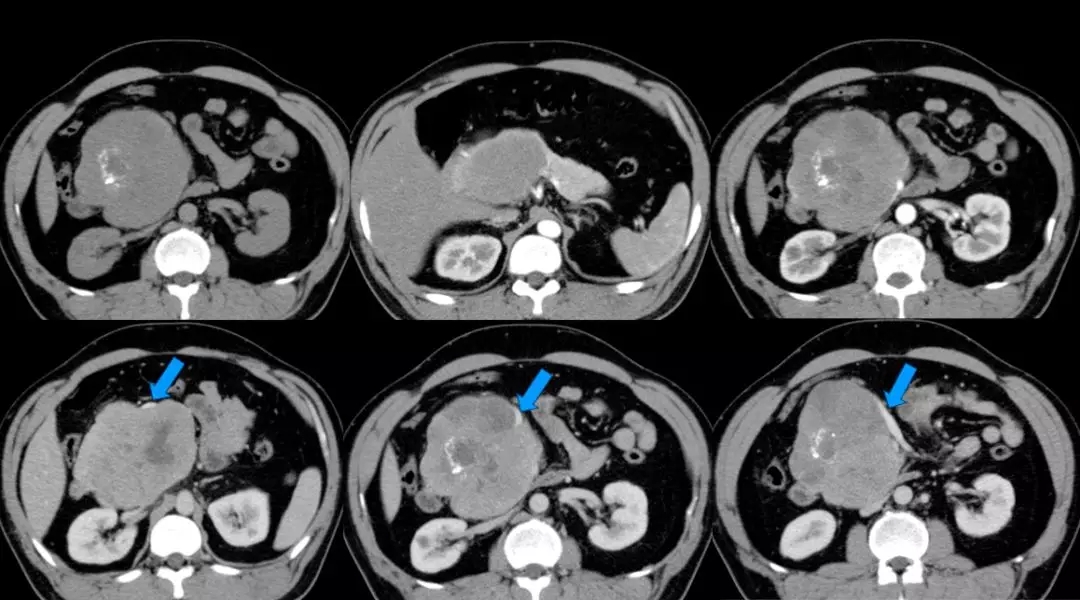

上腹部增强CT:胰头颈体积增大、胰头、颈部可见巨大软组织肿块影,长径约12 cm,与周围分界不清,其内密度不均匀,见片状低密度影及点片状致密影,增强扫描呈不均匀强化,病灶较胰腺实质强化幅度低,其内可见无强化坏死区。腹腔见数个小淋巴结影。脾周可见软组织密度影,长径约1.8 cm,强化方式与脾脏一致。双肾可见多个囊状无强化低密度影。左肺上叶可见斑片状密度增高影,增强可见明显强化。考虑:(1)胰头颈占位,考虑恶性;(2)副脾;(3)双肾多发囊状;(4)左上肺病变,炎症可能。(蓝色箭头为受侵PV-SMV)

数字化血管三维成像:(1)胰腺头颈部及相邻体部囊实性肿瘤,考虑实性假乳头状瘤可能大,相邻血管及十二指肠明显受压,门静脉主干旁个别淋巴结肿大;(2)副脾;(3)双肾多发囊肿

术后上腹部增强CT血管重建显示门静脉通畅,肝脏血供良好